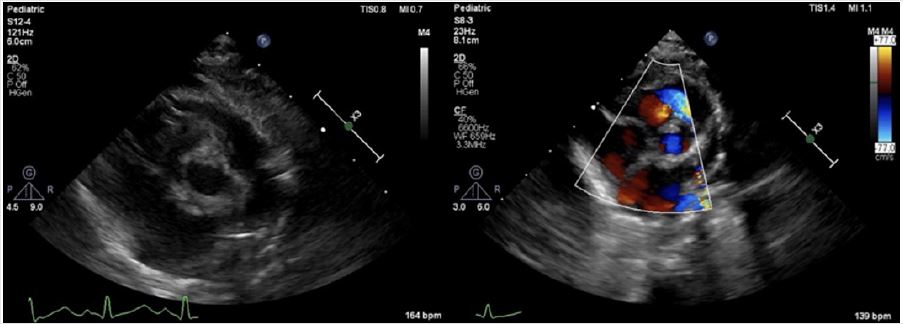

A four-month-old male infant weighed 3.5kg was admitted to our hospital due to cardiac soufflé was found two months ago. The patient presented with a graded 3/6 systolic murmur without palpable thrill, developmental retardation and weight gained slows down refers to peer infants. Preoperative transthoracic echocardiography (TTE) confirmed it was narrow upper the aortic valve with the narrowest part was the sinus canal junction and the diameter was about only 4mm with blood flow accelerated considerably (Figure 1A), pulmonary value annulus diameter was about 7mm with normal trunk and branch, pulmonary blood flow accelerated as well (Figure 1B). Other preoperative examinations showed no significant abnormalities. Then, surgical aortic and pulmonic stenosis correction under cardiopulmonary bypass (CPB) was planned.

Figure 1A: Preoperative TTE. Preoperative TTE demonstrated it was narrow upper the aortic valve, and the narrowest part was the sinus canal junction with the diameter was about only 4 millimeter(mm), inner diameter of ascending aorta was about 8mm, the ventricular septum and posterior wall of left ventricle were thickened. The blood flow accelerated with the Vmax was 4.8m/s and PGmean was 57mmHg.

Figure 1B: Preoperative TTE. Pulmonary value annulus diameter was about 7mm with normal trunk and branches. The blood flow accelerated with the Vmax was 3.3m/s and PG mean were 43mmHg.